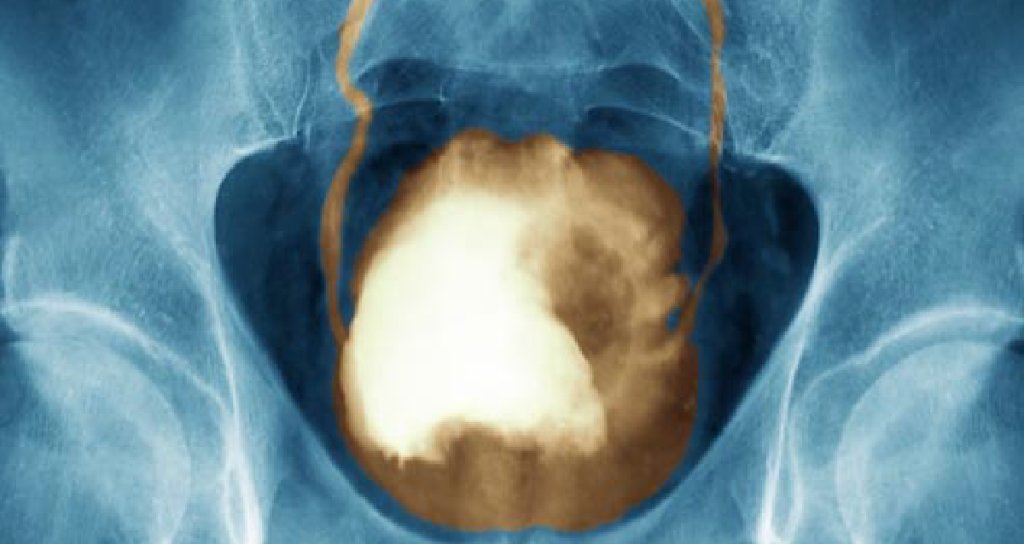

The urinary bladder is an organ that stores the urine. Blood in urine (hematuria), which may cause urine to appear bright red or cola colored, though sometimes the urine appears normal and blood is detected on a lab test Kidney cancer may also be felt as a lump on the back or side, something that generally does. In most cases, blood in the urine (called hematuria) is the first sign of bladder cancer. Bladder cancer can often be mistaken for a urinary tract infection, because many of the symptoms overlap.

In most cases, blood in the urine (called hematuria) is the first sign of bladder cancer.there may be enough blood to change the color of the urine to orange, pink, or, lessoften, dark red. Up to 90% of new diagnoses of bladder cancer are made by noticing blood in the urine and running tests to determine where it comes from. There are other symptoms to watch for as well. But, because kidney cancer occurs upstream from the bladder, any pain tends to be located further up the back to one side. The most common kind of bladder cancer is a cancer called transitional cell carcinoma (tcc).